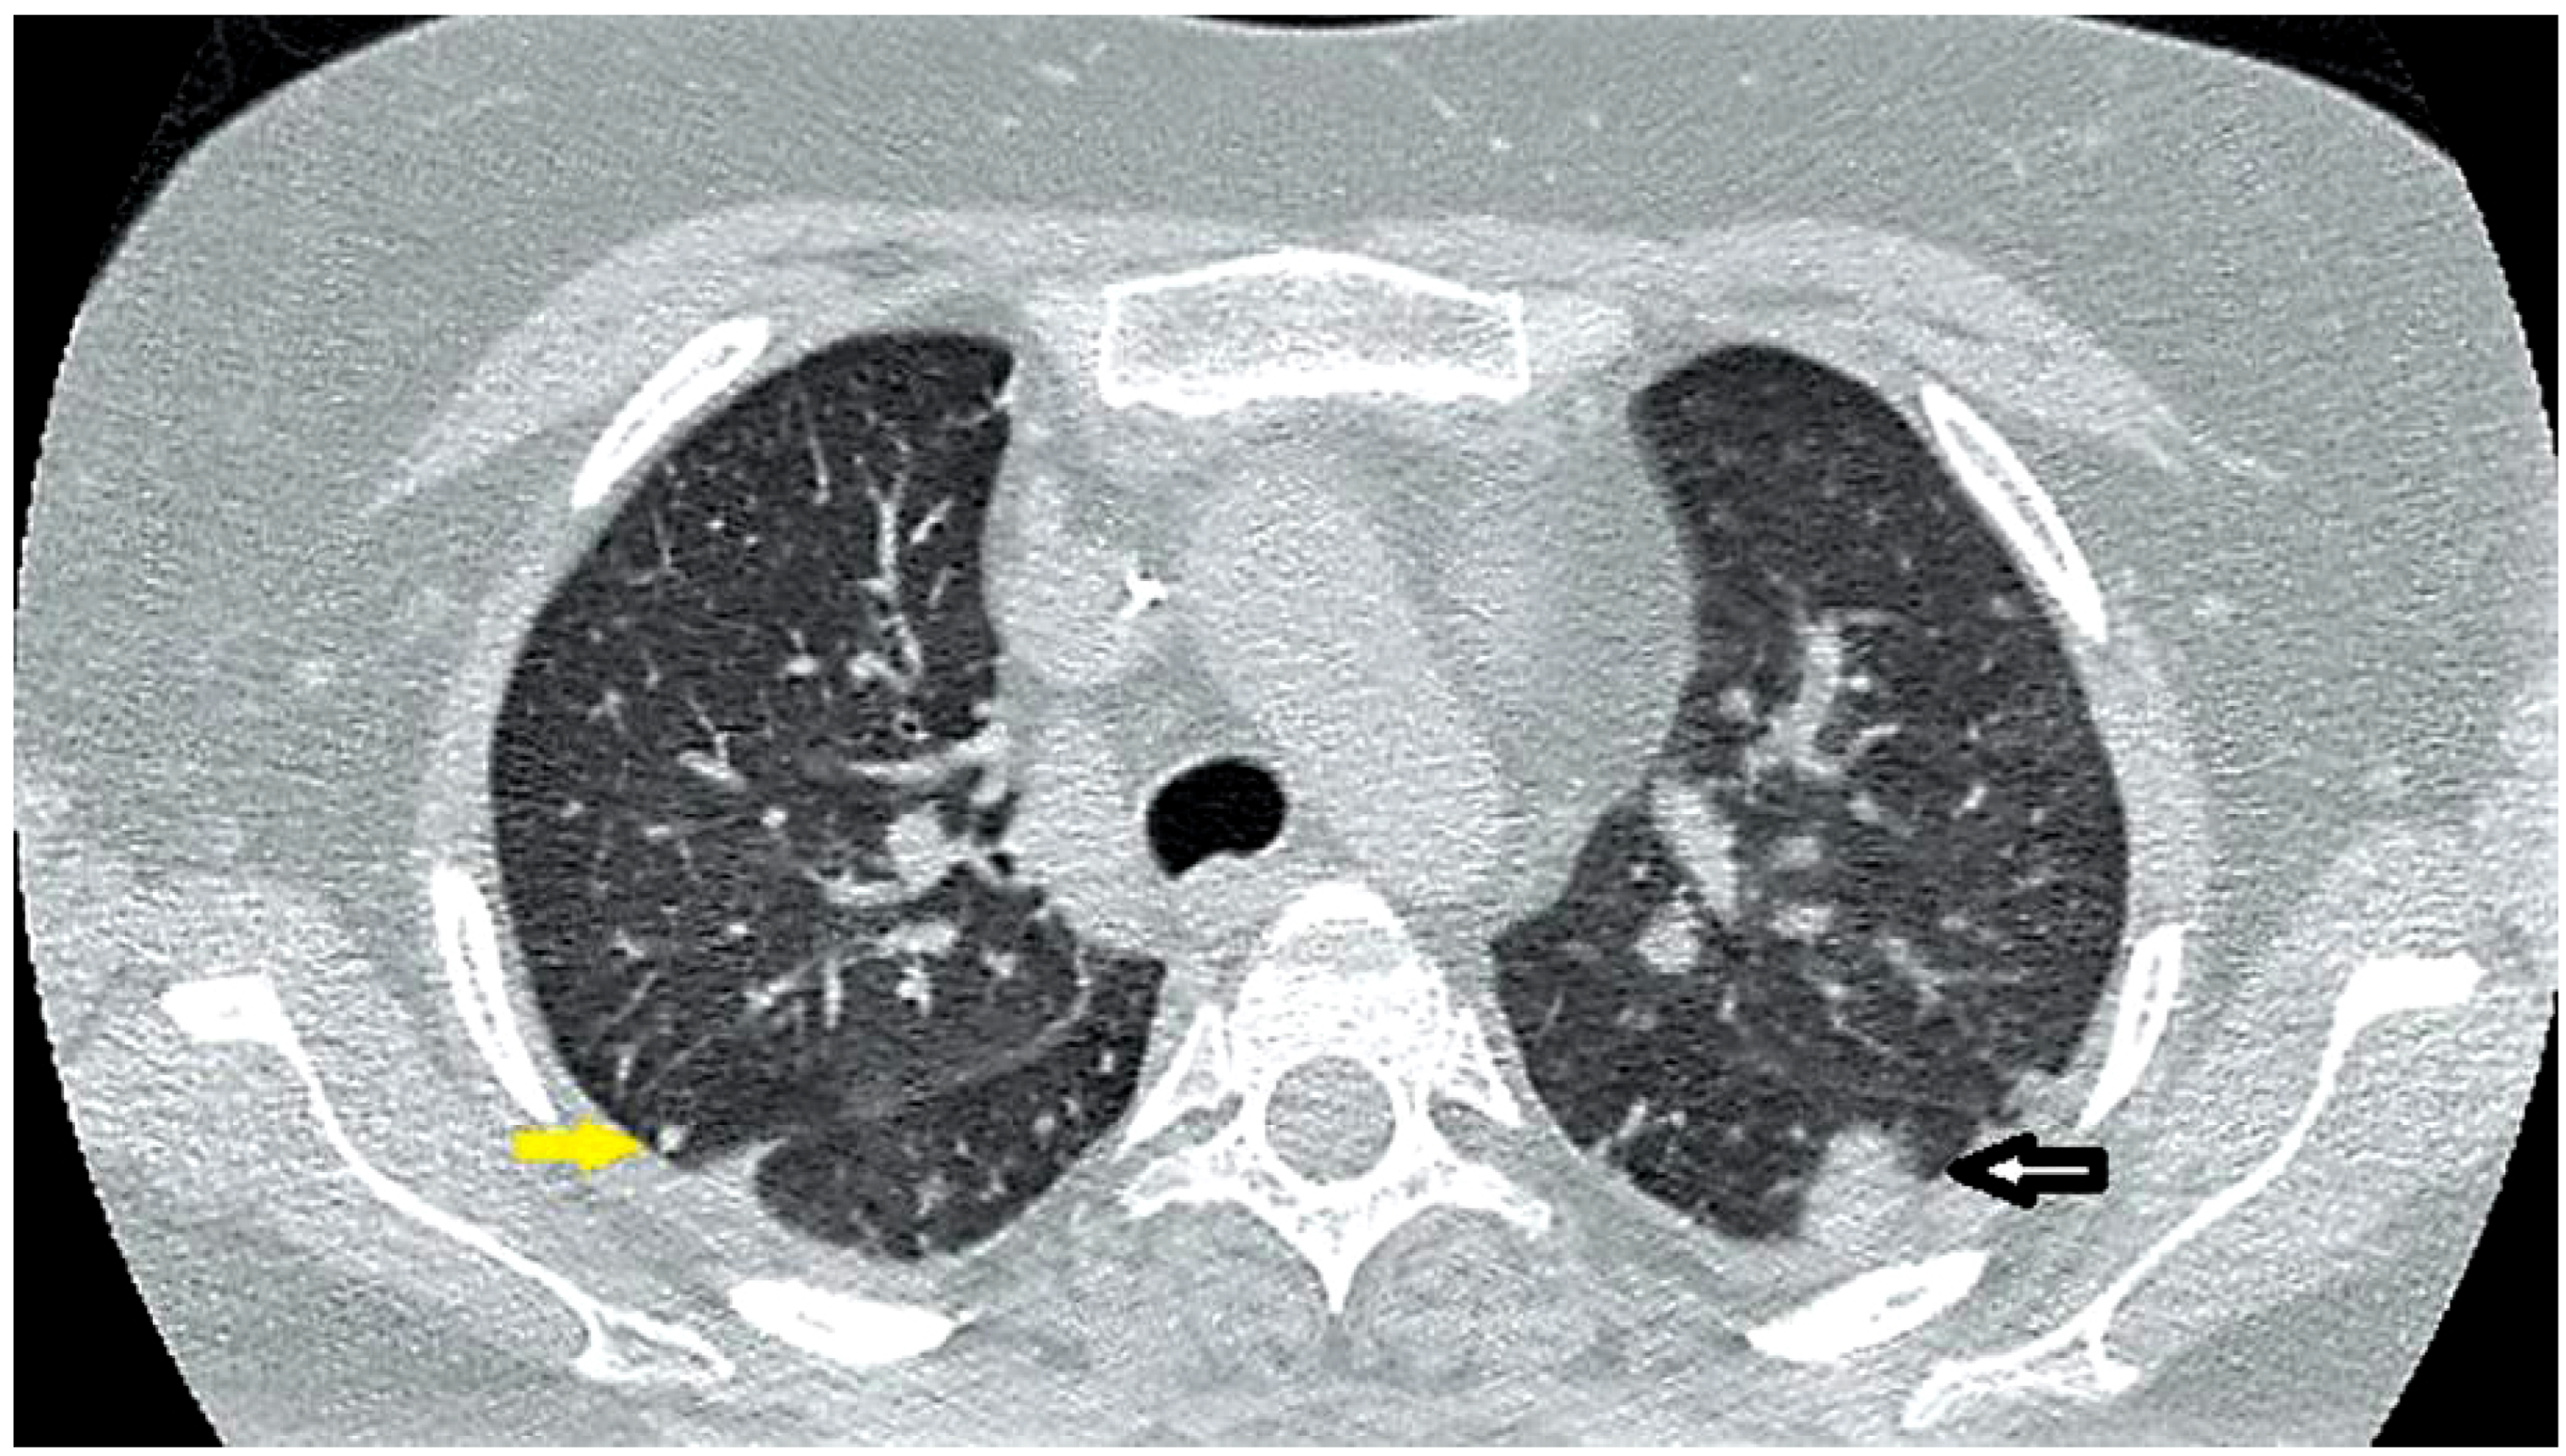

Additional negative tests included serum galactomannan and β-d-glucan, serology for Cryptococcus, Histoplasma, Blastomyces and Coccidioides, CMV PCR, EBV PCR as well as fungal, mycobacterial and bacterial blood cultures. As the patient’s condition slightly improved, antimicrobials were stopped and she was discharged. At regular outpatient evaluation, she continued to complain of episodes of fever and fatigue which partially improved with dexamethasone. Three weeks later, the patient was re-admitted due to a new episode of fever. Physical exam showed mild splenomegaly. Laboratory tests were remarkable for persistent pancytopenia, and the mycobacterial blood culture taken from the previous admission (three weeks earlier) returned positive for Mycobacterium avium complex. A repeat CT chest showed further enlargement of pulmonary nodules and infiltrates (Figure 2). Anti-mycobacterial treatment was started with clarithromycin 500 mg twice daily, ethambutol 15 mg/kg daily and rifabutin 300 mg daily. Also, progressive reduction of dexamethasone dose was scheduled. Within 1 week of treatment, fever subsided and the patient was discharged in stable condition. Six weeks later, the patient was evaluated in the clinic and remained afebrile, neutropenia had resolved and a repeat CT scan of the chest showed marked improvement of pulmonary lesions. She was doing well at 6 months follow up.

Figure 2.

Chest CT showing a peripheral nodule (yellow arrow) and irregular focal infiltrate (white arrow).